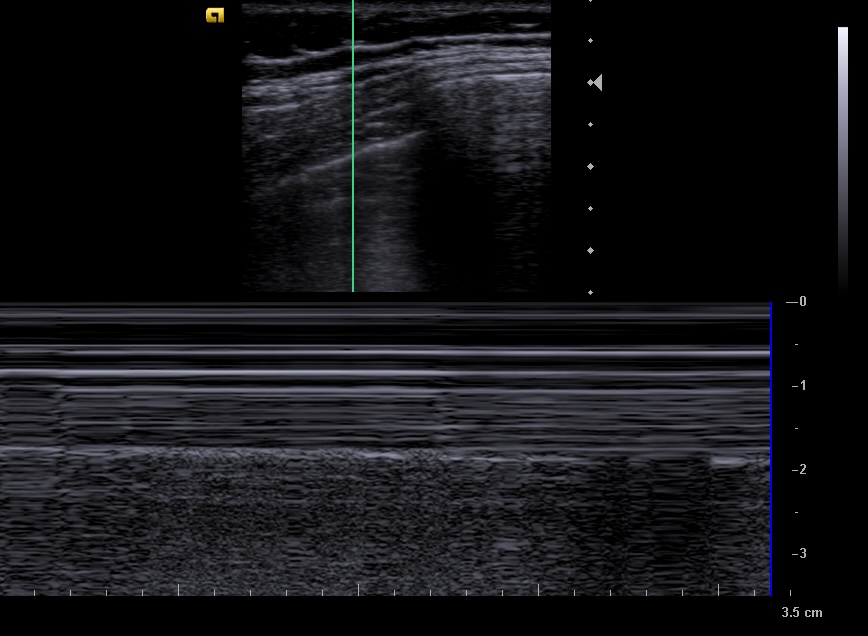

En la ecografía apreciamos en campo derecho un patrón ecográfico tisular, con líneas y puntos hiperecoicos, y algún artefacto en cola de cometa, correspondientes a broncograma aéreo.

Neumonía no complicada en campo pulmonar derecho.